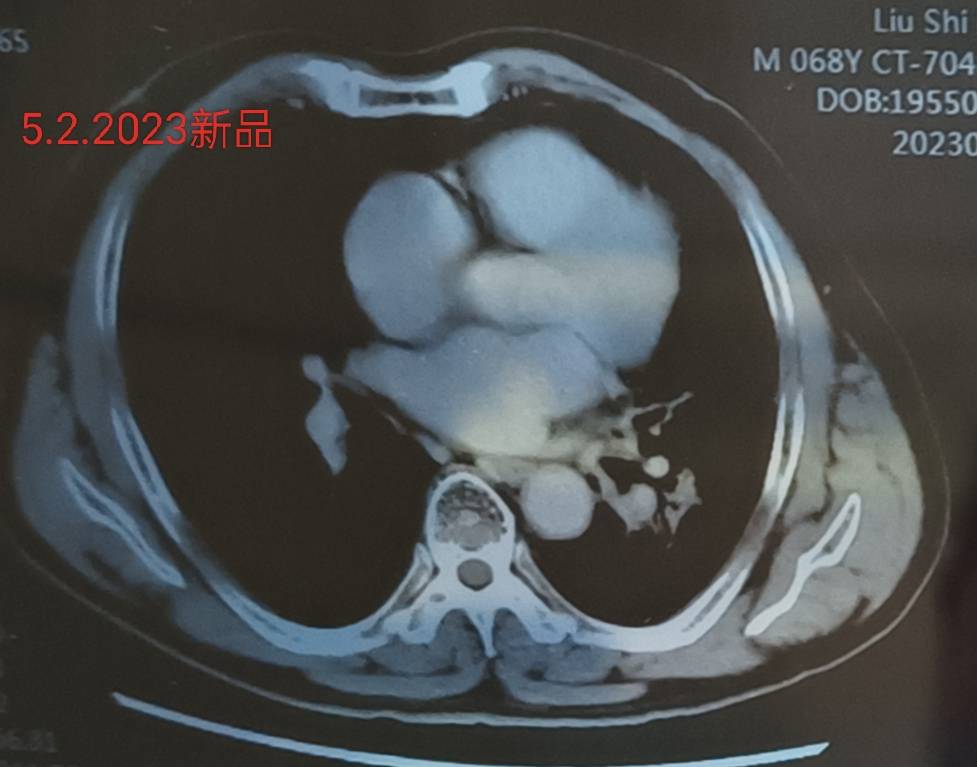

四化放疗后单免半年复查

去拿报告单的时候心如擂鼓,紧张害怕比确诊时更甚!片子上肿瘤区看着应该问题不大。报告单最后才打出来,描述为肿瘤区欠清,不知道为什么但不纠结它。揪着的心还没来得及放下,又看到说左颈部ⅡB区增大淋巴结,均匀强化,医生检查时摸不到,说小于1CM,先观察,也可能是炎症。最近一两个星期老人家说有时候觉得喉咙感觉有东西粘在上面一样,有点不舒服,经常会清一清嗓子,但不怎么咳嗽。会不会是转移?如果是,怎么办?

纵膈肺门小淋巴结倒是一直没动静,估计不是转移了吧。